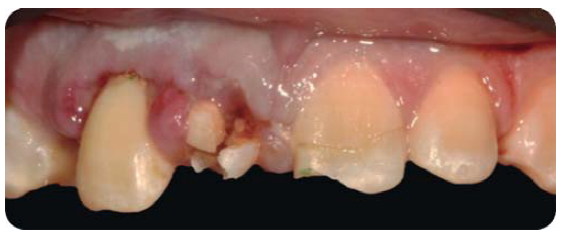

Paciente masculino de 28 años de edad, con LDT en el incisivo central superior derecho por un golpe al desmayarse, previo a un procedimiento quirúrgico para extirpar un tumor que presentaba en el riñón izquierdo, cinco años de evolución.

En la exploración extraoral se observa una cicatriz en el labio inferior (Figura 16), el paciente refiere que, él extrajo el fragmento del incisivo 11 un día después de la LDT.5

Durante la exploración intraoral, se observa una lesión fistulosa a nivel del ápice del diente 11 y el paciente refiere que los síntomas han disminuido con el transcurrir de los años (Figura 17).

Estos signos (Cuadro I) y síntomas, sumados con la imagen radiográfica confirma el daño pulpar del diente 11.

Fractura no complicada de corona del diente 11, presentando necrosis pulpar con periodontitis apical crónica supurativa; gingivitis inducida por placa dentobacteriana y agrandamiento gingival en el diente 12.